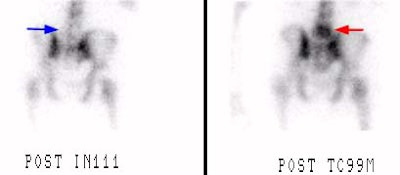

L5 vertebral osteomyelitis:

(Case submitted by Dr. Marc Cote, D.O.)The case below illustrates the decreased sensitivity of In-111 WBC imaging for the detection of vertebral osteomyelitis. The whole body bone scan revealed increased tracer activity within L5. The In-111 WBC exam (shown below with Tc-MDP exam for comparison) demonstrated no evidence of increased tracer accumulation in L5 (blue arrow).